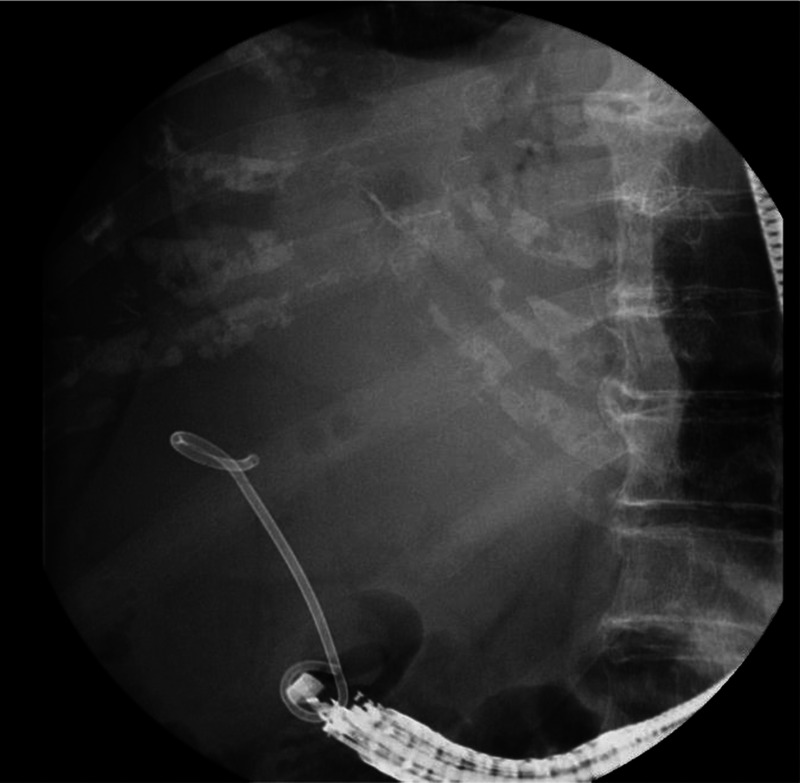

EUS-guided abscess drainage in an elderly patient with an abscess in the right liver lobe (with video).

一名右肝叶脓肿的老年患者在 EUS 引导下进行脓肿引流(附视频)。